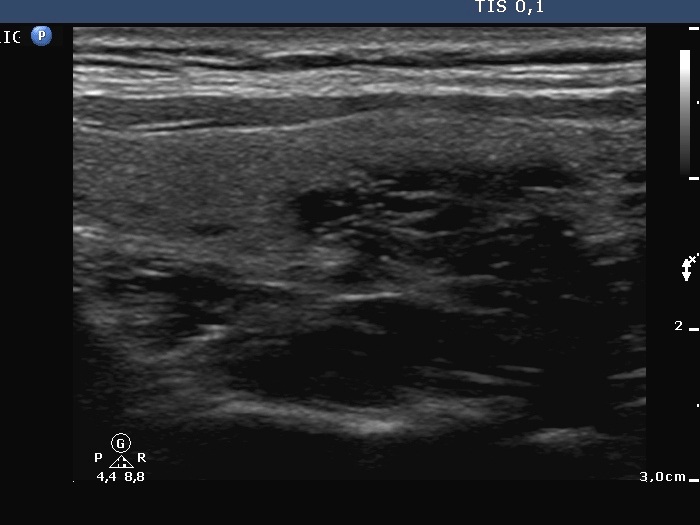

Follow-up examination 17 months after first visit (second and third rows):

Palpation: a hard nodule in the upper part of the left thyroid.

Ultrasonography: The echogenicity index of the thyroid was 50%. The vascularization was not significantly increased. There was a large hypoechogenic, inhomogeneous nodule in the upper part of the left lobe. Both the intranodular and the perinodular blood flows were increased.

1. It seems to be a reasonable assumption that papillary cancer had been already present at the first investigation. It was very unusual that the left thyroid was significantly more inhomogeneous than the right lobe. The former contained relatively large hyperechogenic granules, however, there were no discrete circumscribed lesion in the left lobe.